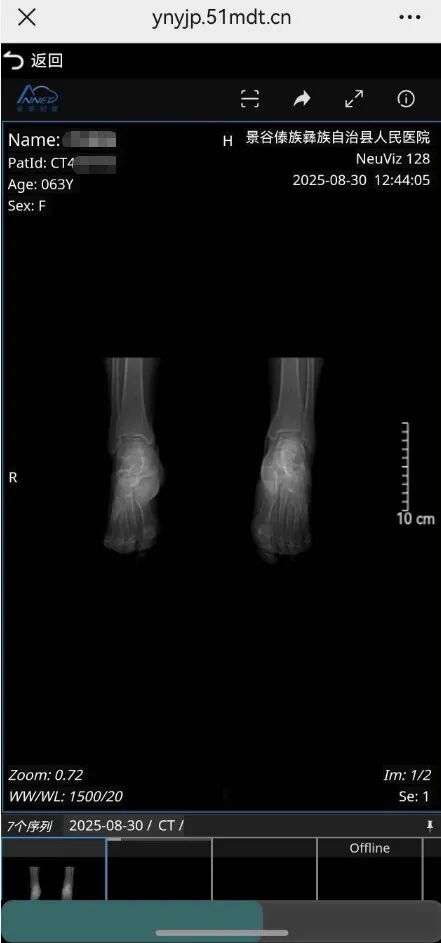

电子云胶片即医学影像数字化服务。完成X光、CT、MRI等检查后,您无需领取传统塑料胶片和纸质报告。所有影像和报告均加密存于云端,可通过移动终端设备(手机等)随时查看、下载和分享,实现“一机在手,影像随身”。